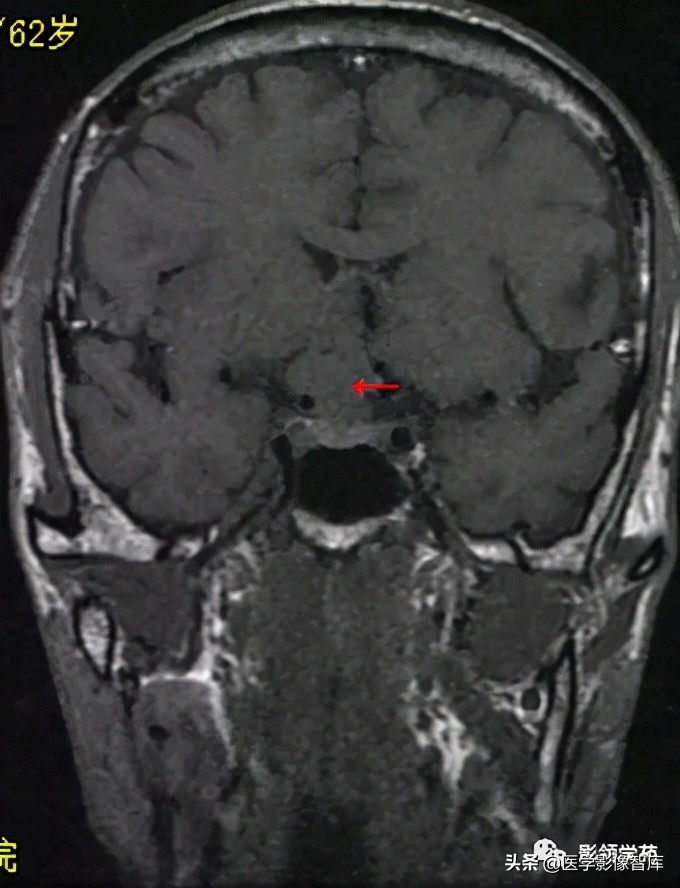

男 62岁,右眼视朦半年

鞍区见一类圆形稍高密度肿块影,密度较均匀,边界较清,位置稍偏右,向上突入鞍上池内,周围骨质未见破坏。

前颅窝底、鞍前区见一肿块影,呈等T1等T2信号,信号均匀,边缘清楚,以宽基底与颅底接触。

病灶呈均匀明显强化(馒头样),见脑膜尾征;肿块后缘部分进入鞍内,挤压垂体前方和视交叉,垂体柄显示不清楚。

右侧大脑前动脉A1段完全被肿瘤包绕;左侧大脑前动脉A1段与肿瘤分界不清,但无明显包绕和推移。双侧海绵窦未见异常征象。